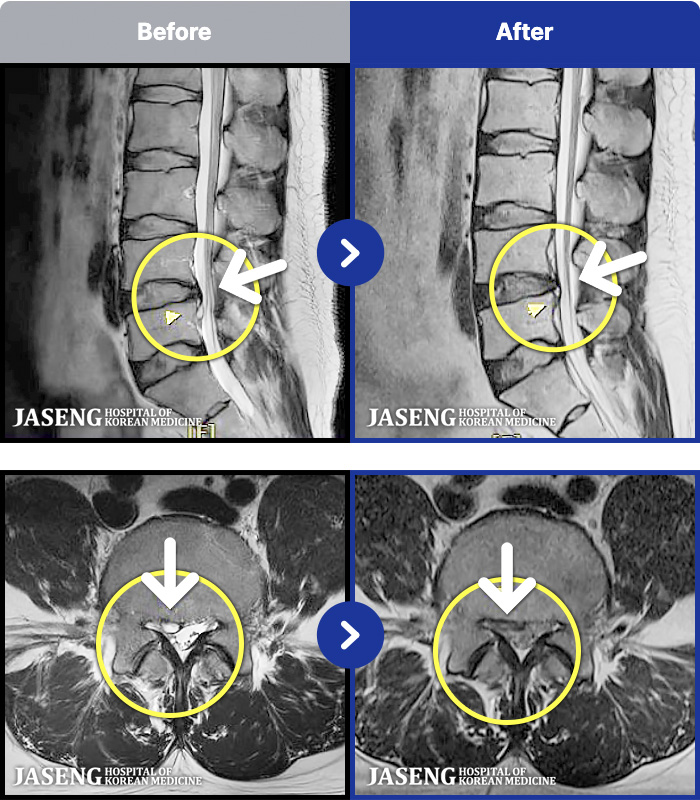

1,293 MRI ũ ʸ Ȯϼ.